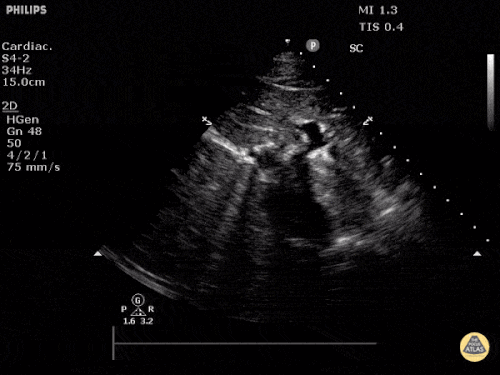

Parasternal kısa aks

Sağ ventrikül fonksiyonunun değerlendirilmesi

Sağ ventrikül, önceki bölümde anlatılan temel kardiyak pencereler kullanılarak değerlendirilebilir. Normalde sağ ventrikül düşük basınçlı bir odacıktır ve sol ventriküle kıyasla daha küçük görünür.

Sağ ventrikül disfonksiyonunda özellikle şu bulgulara bakılır:

Sağ ventrikül dilatasyonu

Septal bombeleşme (septal bowing)

Kısa aks görüntüsünde, pulmoner arter basıncının artmasına bağlı olarak sağ ventrikül genişledikçe interventriküler septum sol kalbe doğru bombeleşir. Bu durum sol ventrikülde D-şekilli görünüm (D-sign) oluşturur.

Apikal dört boşluk görüntüsünde sağ ventrikül normalde sol ventrikülün yaklaşık üçte ikisi büyüklüğünde olmalıdır. Eğer iki ventrikül aynı boyutta görünüyorsa bu durum anormal kabul edilir ve dilatasyon düşündürür.

Bir diğer önemli bulgu McConnell belirtisidir. Bu bulgu, sağ ventrikül serbest duvarında hipokinezi bulunurken apeksin korunmuş olması şeklinde tanımlanır.

Önemli bir hata, sağ ventrikül disfonksiyon bulgularını otomatik olarak akut bir sürece (örneğin pulmoner emboli) bağlamaktır. Yukarıda belirtilen bulgular hem akut hem de kronik durumlarda görülebilir. Bu nedenle klinik bağlam ve hasta öyküsü önemlidir. Önceden yapılmış bir ekokardiyografi raporu, yatak başı değerlendirme ile karşılaştırma yapmak açısından çok yardımcı olabilir.

Apikal dört boşluk görüntüsü alınırken dikkatli olunmalıdır. Eğer görüntü aks dışı alınırsa sağ ventrikül kısalmış (foreshortened) görünebilir ve dilatasyon gözden kaçabilir. Bu hatadan kaçınmak için probu hafifçe döndürerek sağ kalbin en geniş göründüğü düzlemi yakalamak gerekir.